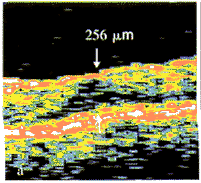

图1 a.黄斑区内界膜反光增强,黄斑区厚度增加,中心凹神经上皮层内可见小暗区(箭)。提示黄斑区水肿,视网膜前膜形成;b.可见黄斑区反光稍强,未见其它异常。图中箭示OCT扫描轴位 图2 a.黄斑区视网膜神经上皮层增厚,可见小暗区(双箭),鼻侧见玻璃体后界膜反光带并向黄斑延伸(单箭),提示黄斑水肿合并玻璃体后脱离;b.可见黄斑区反光稍强。图中箭示OCT扫描轴位 图3 a.黄斑区神经上皮层部分断裂(箭),其下可见部分视网膜组织,提示黄斑囊样破裂所致的板层裂孔;b.黄斑区可见黄白色漆样裂纹,中心凹可见一暗红色灶内有一黄白色小点。图中箭示OCT扫描轴位 图4 a.视网膜色素上层层连续性破坏(箭),提示黄斑视网膜色素上皮损伤;b.黄斑区可见少许黄白点状渗出,未见其它异常。图中箭示OCT扫描部位